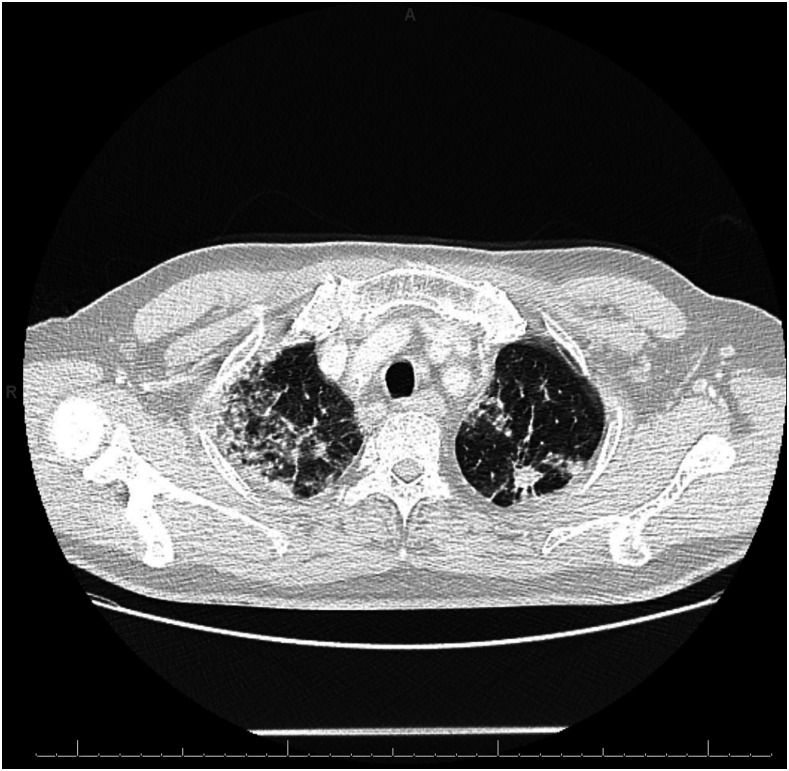

On presentation, the patient was in no acute distress. He was afebrile. Oxygen saturation was 94% on room air. Pulmonary examination was normal. His laboratory findings revealed a white blood cell (WBC) count of 11.5 cells × 109/L with 1.7% eosinophils (absolute eosinophil count of 0.2 cells × 109/L). Liver enzymes were normal. Chest X-ray showed bilateral airspace opacities, with focal consolidation in the right upper lobe and at the bases (Figure 1). Computed tomography of the chest with contrast showed multifocal reticular and ground-glass opacities, an 11-mm spiculated nodular mass within the left apex, and associated bulky mediastinal and hilar lymphadenopathy (Figure 2).

Figure 2.

Computed tomography of the chest. Initial Computed tomography of the chest with contrast showed multifocal reticular and ground-glass opacities, an 11-mm spiculated nodular mass within the left apex, and associated bulky mediastinal and hilar lymphadenopathy.